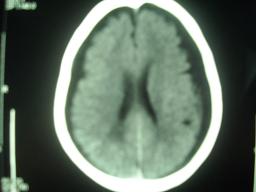

外伤性硬膜下积液(traumatic subdural effusion, tse)又名外伤性硬膜下水瘤, tse好发于60岁以上老年人,这与老年人存在不同程度脑萎缩、硬膜下间隙增大有关。根据颅脑损伤病史,伤后头痛、头晕、恶心、呕吐等症状,及ct扫描表现为单侧或双侧颅内骨板侧低密度,呈弧形或新月形,与脑组织边界清楚,tse不难诊断

外伤性硬膜下积液(traumatic subdural effusion, tse)又名外伤性硬膜下水瘤, tse好发于60岁以上老年人,这与老年人存在不同程度脑萎缩、硬膜下间隙增大有关。根据颅脑损伤病史,伤后头痛、头晕、恶心、呕吐等症状,及ct扫描表现为单侧或双侧颅内骨板侧低密度,呈弧形或新月形,与脑组织边界清楚,tse不难诊断。very good!